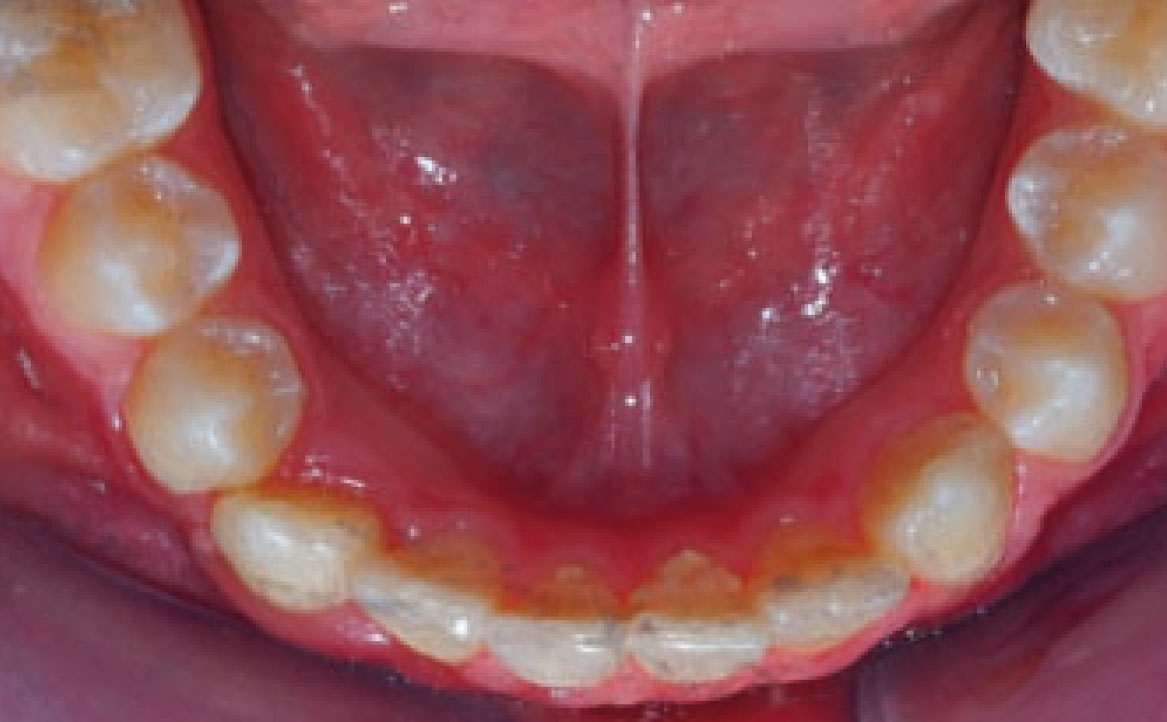

Dall’esame obiettivo intra orale si osservava una seconda classe canina destra e sinistra, una seconda classe molare destra e sinistra, e un diametro inter-canino e inter-molare ridotto sia in riferimento al mascellare superiore sia al mascellare inferiore (fig. 3A-3E).

Al fine di ottenere un’espansione delle arcate, nella fase iniziale, è stato posizionato un espansore rapido palatale sull’arcata superiore e un arco linguale a livello dell’arcata inferiore per permettere le estrazioni dei denti decidui compromessi.

Terminata la prima fase, all’età di 11 anni, il paziente è stato rivalutato tramite gli esami radiografici. Dall’OPT si osservava la presenza della dentatura permanente, con prossima esfoliazione dei settimi, oltre alla formazione delle gemme degli elementi 18-28-38-48 (fig. 4).

A seguito del trattamento è stato osservato un miglioramento dell’igiene orale (fig. 5).

Clinical examination revealed high caries risk, poor oral hygiene, and constricted upper and lower arches.